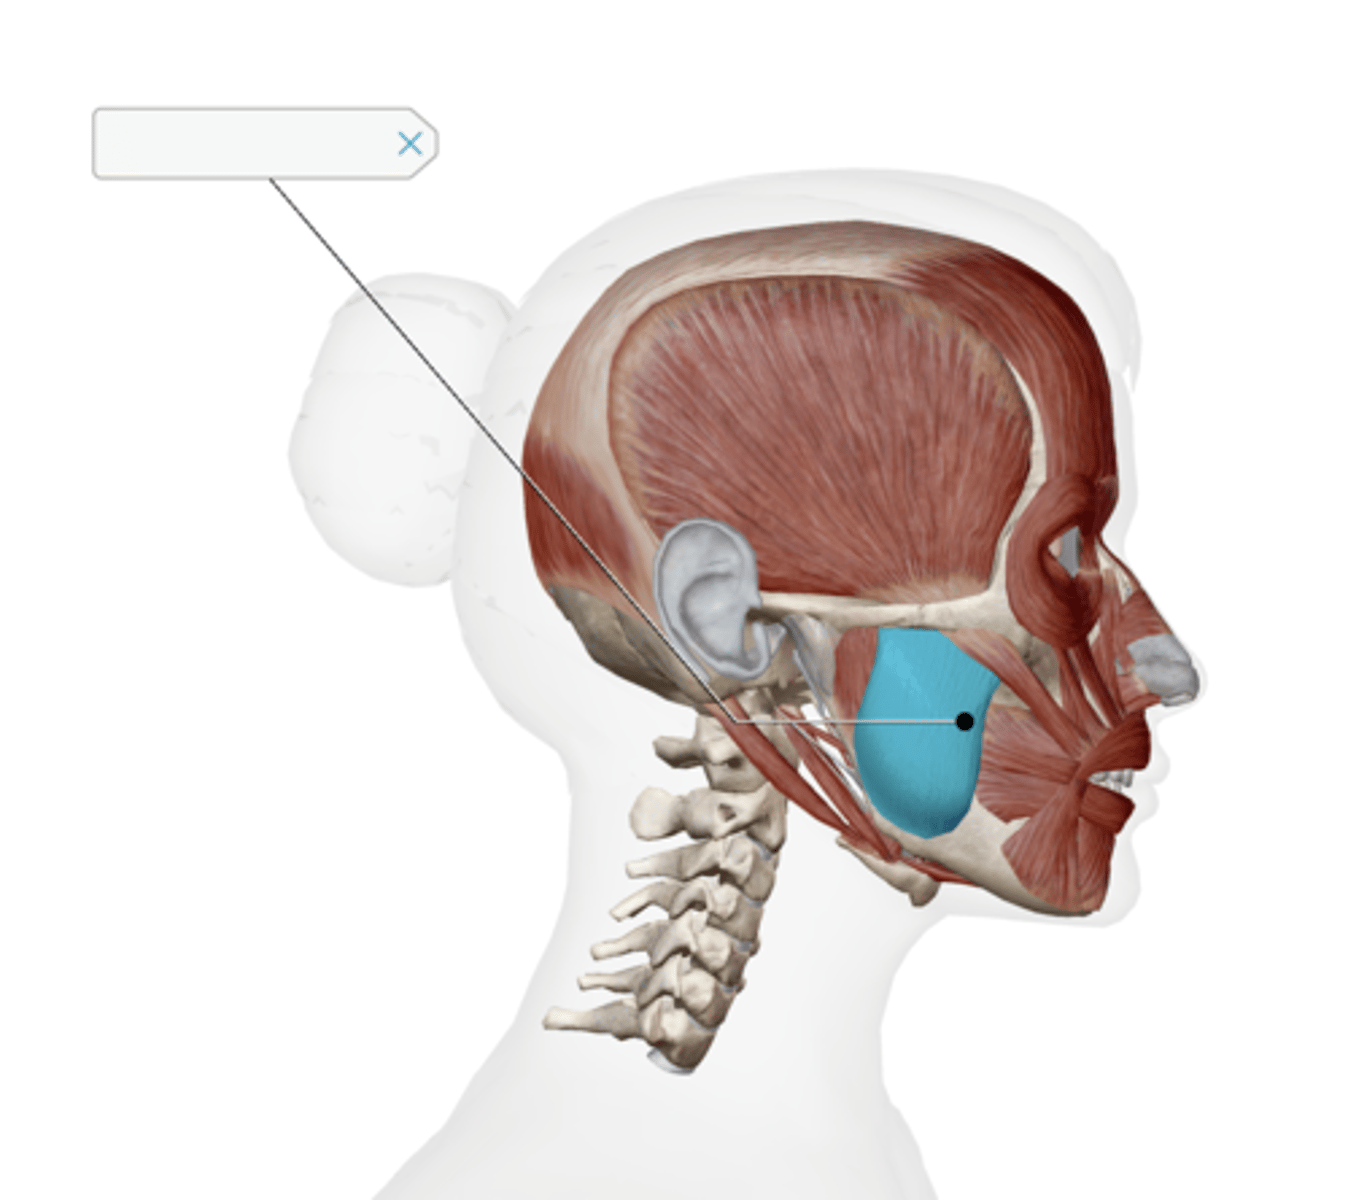

Parotid gland

Superficial masseter

Deep masseter

Temporalis